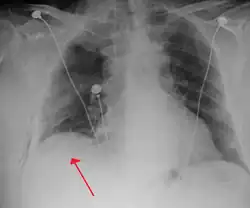

Radiografía

Una radiografía realizada en proyección postero-anterior (de atrás hacia delante) y durante la inspiración máxima constituye la forma de diagnóstico más frecuente.[38] Las imágenes realizadas en espiración, al contrario, no poseen valor diagnóstico significativo,[20] aunque pueden resultar útiles cuando existe una alta sospecha de neumotórax, pero la radiografía en inspiración aparece normal.[39] Si este es el caso, también pueden realizarse radiografías de proyección lateral, aunque esta práctica no se realiza con frecuencia.[20][31]

-

radiografía anteroposterior que muestra un neumotórax de reducido tamaño en el pulmón izquierdo, causado por una punción -

Radiografía lateral en inspiración, que muestra el neumotórax en la parte posterior -

Radiografía anteroposterior en espiración en la que también puede observarse el neumotórax

A veces puede darse una desviación del mediastino hacia el lado contrario en el que se halla el neumotórax debido a las diferencias de presión que crea esta patología. La presencia de esta desviación no implica la existencia de un neumotórax a tensión, que habitualmente se diagnostica a través de signos de gravedad como hipoxia severa y choque obstructivo.[30]

El tamaño del neumotórax (es decir, la cantidad que este ocupa en la cavidad pleural) puede determinarse midiendo la distancia entre la caja torácica y el borde del pulmón. Esto es de relevancia para el tratamiento, ya que los neumotórax de menor tamaño a menudo poseen un enfoque terapéutico distinto. Una distancia de dos centímetros significa que el neumotórax ocupa un 50 % del hemitórax.[20] Las guías de práctica clínica afirman que esta medida debe darse a partir del hilio pulmonar, con un umbral de referencia de dos centímetros para indicar la presencia de un neumotórax de menor o mayor tamaño. La medida también puede realizarse a partir del ápice pulmonar, y en este caso el umbral es de tres centímetros,[40] aunque esta forma de medición puede hacer pensar que el tamaño del neumotórax es mayor si este se encuentra concentrado en la parte superior de la caja torácica.[20][31] Aun teniendo en cuenta esto, estos métodos de medida no poseen una correlación perfecta con el tamaño del neumotórax y, aunque el TAC ofrece imágenes más precisas en este sentido, se desaconseja su uso en estas situaciones clínicas.[20]

No todos los neumotórax son uniformes; algunos ocupan solamente un pequeño espacio en un espacio particular de la cavidad pleural.[20] A veces, pueden hallarse pequeñas cantidades de líquido en la radiografía (hidroneumotórax), que puede estar constituido por sangre (hemoneumotórax).[30] En algunos casos la única manifestación de estos que se da en la radiografía es el signo del surco profundo, por el cual se da un aumento del espacio entre la caja torácica y el diafragma por la presencia de líquido.[35]